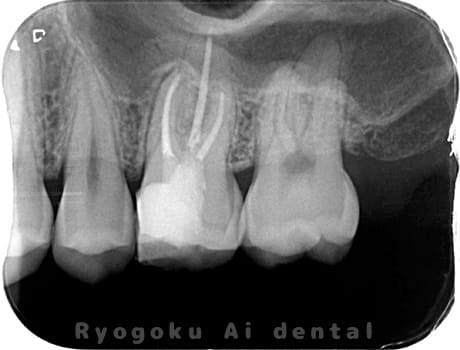

Case04

-

- 原因

- 慢性根尖性歯周炎

- 治療期間

- 3ヶ月

- 治療内容

- マイクロエンド

- 治療費用

- 121,000円

噛むと痛みが出る、とのことで来院した患者様です。他院での根管治療を終えてましたが、根尖病変を認めるため、マイクロエンドを行いました。